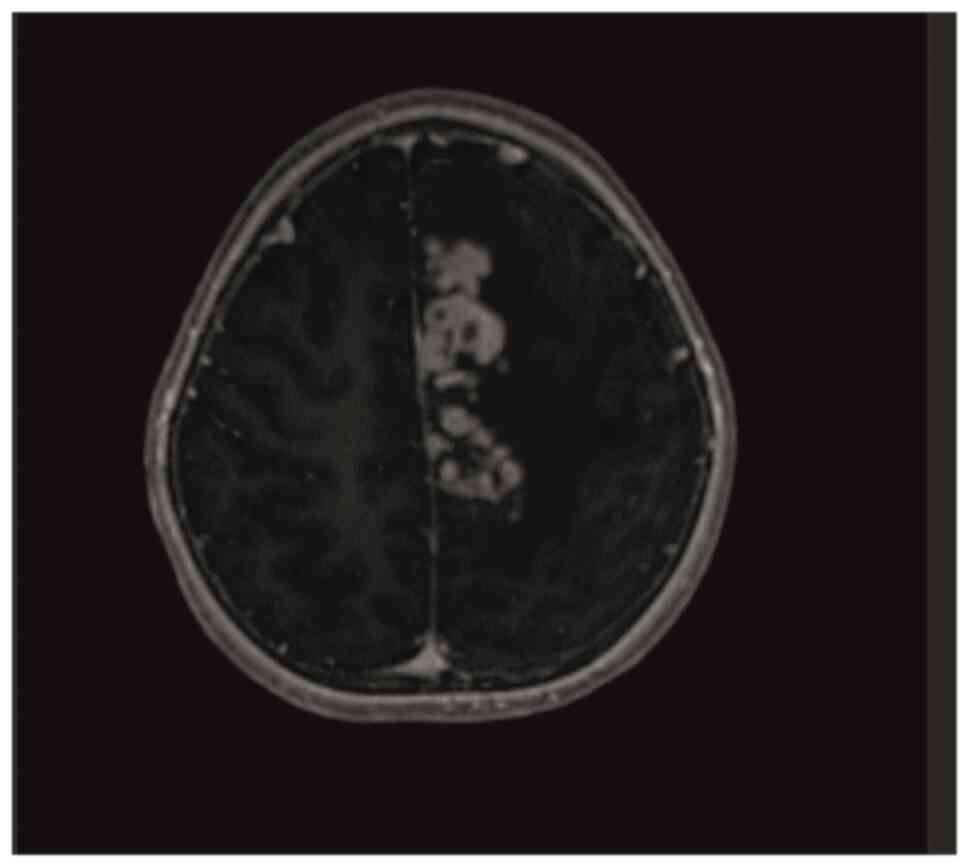

Intracranial tuberculoma represents one of the most severe complications of central nervous system tuberculosis (TB), with an incidence that is relatively low. In cases of intracranial tuberculoma, patients may develop drug toxicity and/or immune reconstitution inflammatory syndrome (IRIS) while receiving anti‑TB treatment. The current study presented the case of a seven‑year‑old female patient with intracranial tuberculoma who developed drug‑induced hepatotoxicity and IRIS during the course of treatment. During the follow‑up of the patient, anti‑TB drug‑induced hepatitis developed, which led to the discontinuation of the drug twice. In the seventh month of treatment, cranial MRI showed the progression of tuberculoma lesions. The possibility of IRIS or treatment failure was considered and the treatment was restarted with steroids and non‑hepatotoxic anti‑TB drugs. With steroid and anti‑TB treatment, the lesions regressed almost completely and the neurological deficit regressed. Patients receiving treatment should be followed up closely due to the possible side effects of anti‑TB drugs, especially IRIS, which develops as an immune restructuring response during the recovery of the immune system.

Figure 1

Figure 2

Figure 3

Figure 4

Figure 5